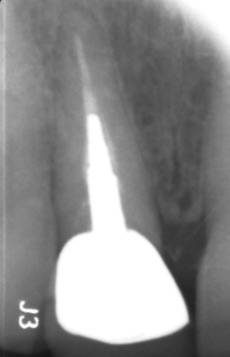

Ein Implantat trägt nicht nur zur Wiederherstellung von Kaufunktion und Ästhetik bei, sondern schützt auch den Kieferknochen vor Abbauprozessen, die nach Zahnverlust auftreten können. Voraussetzung für den langfristigen Erfolg ist eine sorgfältige Planung unter Berücksichtigung von Knochenangebot, Weichgewebe, Funktion und individueller Belastung.

Mithilfe moderner Diagnostik, mikrochirurgischer Techniken und gewebeschonender Verfahren schaffen wir optimale Voraussetzungen für eine sichere Einheilung. Bei Bedarf werden knochenaufbauende Maßnahmen und biologische Regenerationskonzepte integriert, um auch in anspruchsvollen Situationen stabile Ergebnisse zu erzielen.